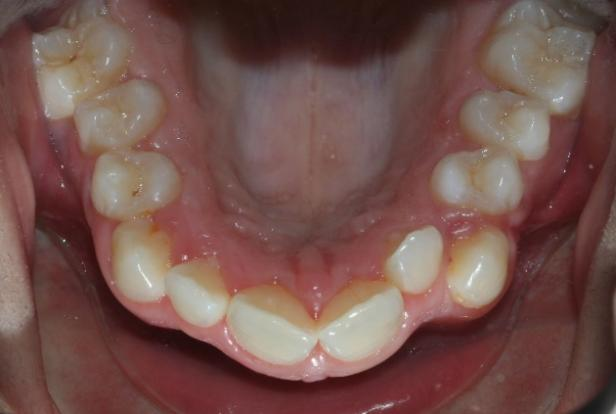

The patient in this case is a 15-year-old female who presented with mild third skeletal class with upper and lower tooth crowding at the beginning of the treatment. The whole process lasted for around 20 months employing traditional metal brackets.

Fig 1,2,3: the intraoral condition before orthodontics treatment & Fig 4,5,6: the intraoral condition after orthodontics treatment.